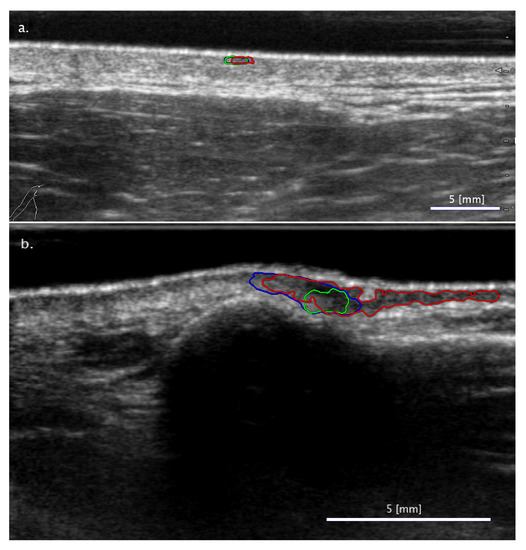

3.2.1. Cases When FA Fails While SA Methods Perform Correctly

3.2.2. Cases When the Two SA Methods Return Different Classifications